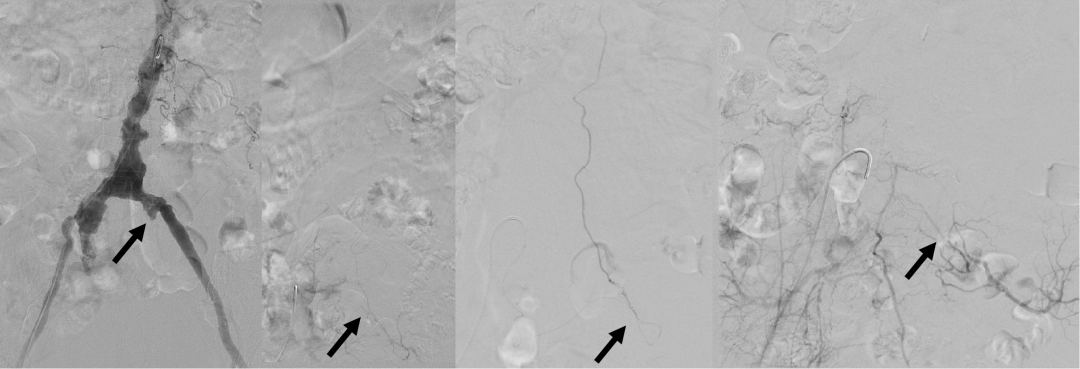

脊髓血管造影检查及手术栓塞

介入手术由吕宪利主刀,张培海、梁士凯辅助,术中,吕宪利在透视引导下,使用超细的微导丝穿过患者严重迂曲钙化的髂内血管,到达动静脉畸形所在的瘘口处,小心谨慎进行畸形血管栓塞,历经2小时顺利结束。麻醉清醒后,患者自觉下肢麻木疼痛感消失,术后1天即实现独立下地行走。“太感谢你们了,欢迎来内蒙旅游!”她激动地向医师们连连道谢。